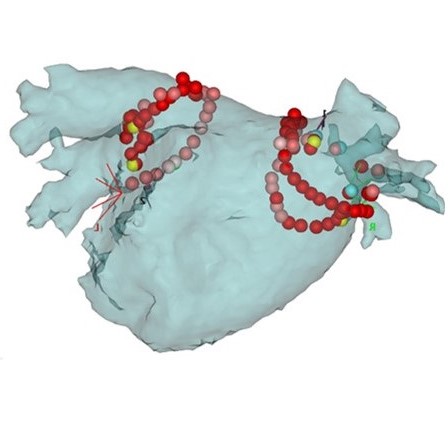

心房細動アブレーション治療(透視像)

心房細動アブレーション治療

(3Dマップに焼灼店表示)